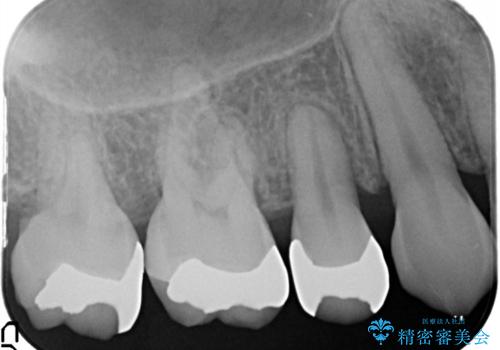

- 笑ったときに銀の詰め物が見えることを主訴に来院されました。

セラミックインレーにて修復を行いました。

保険治療で使える材料には制限があり、見た目だけでなく精度でも劣ります。当院でのセラミックインレーは歯とのつなぎ目を拡大鏡で確認して精度高く仕上げるため、むし歯のリスクを限りなく少なくできるよう治療します。